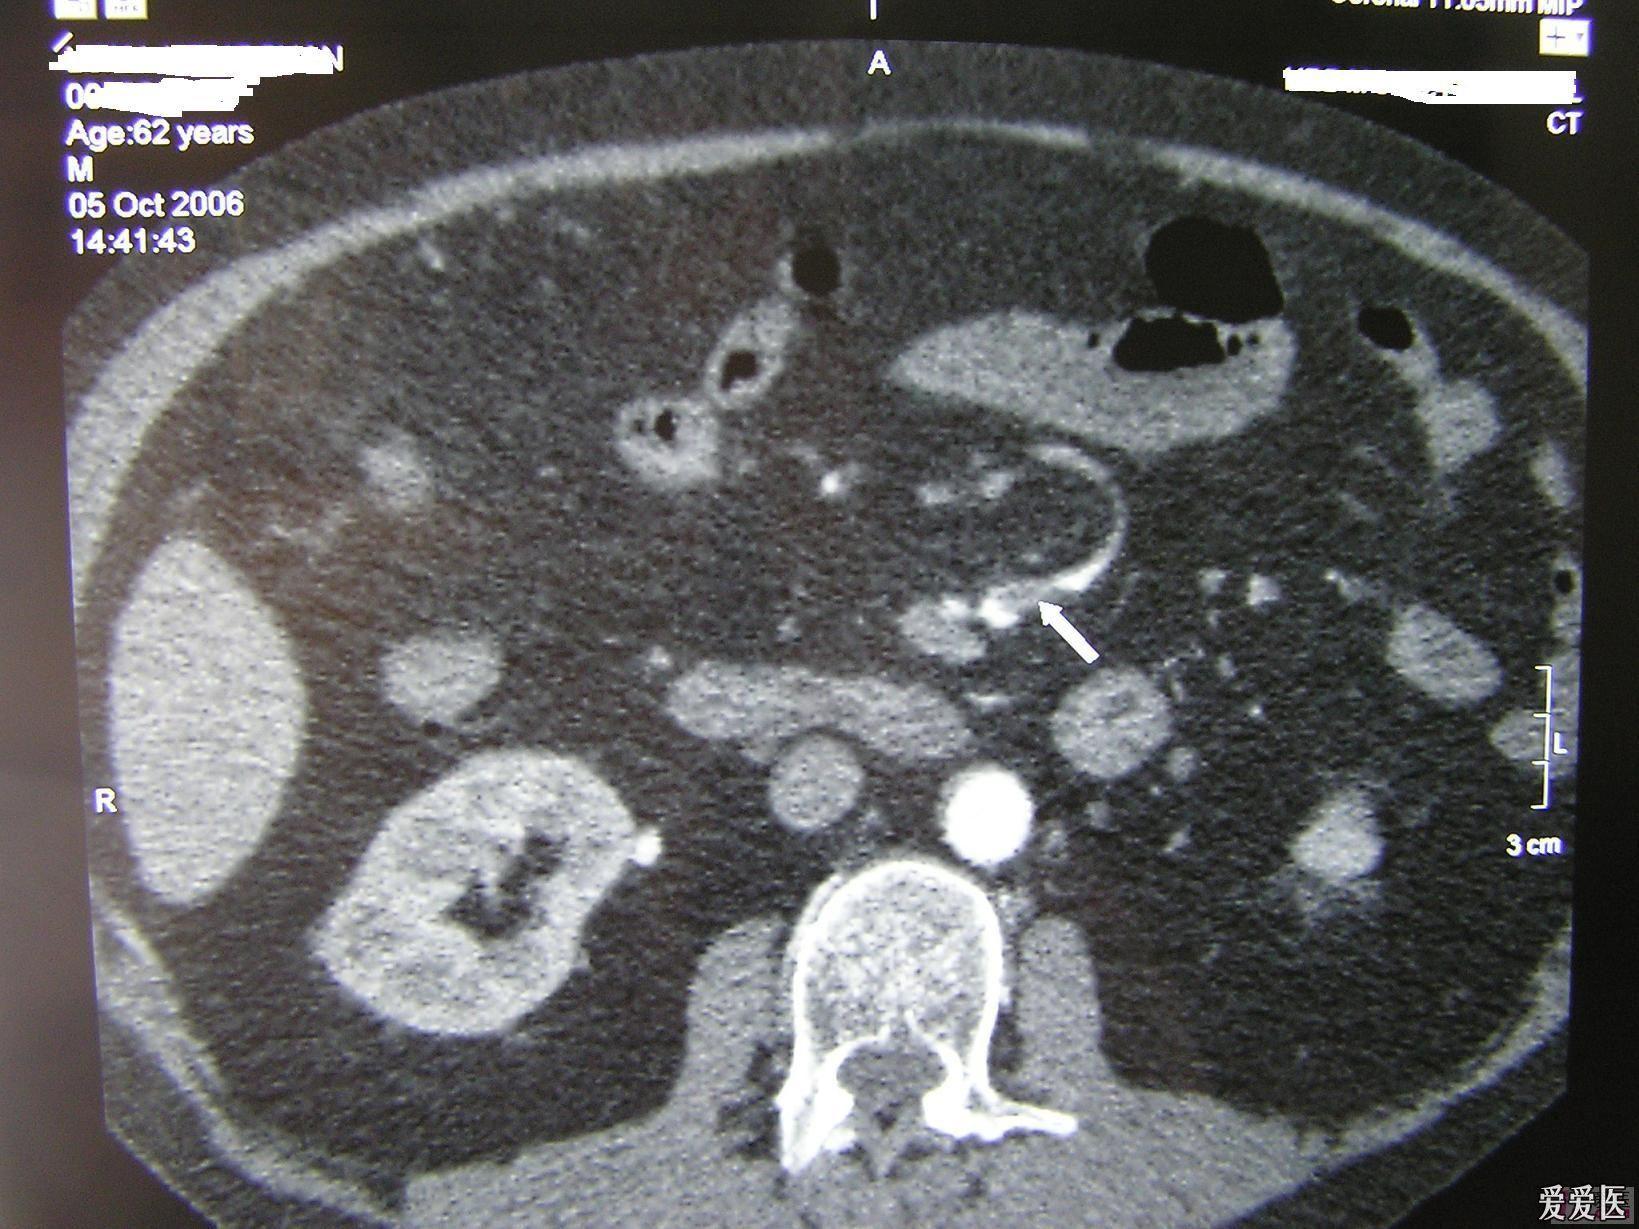

【病例】肠系膜上动脉栓塞2例ct影像

图片尺寸962x768